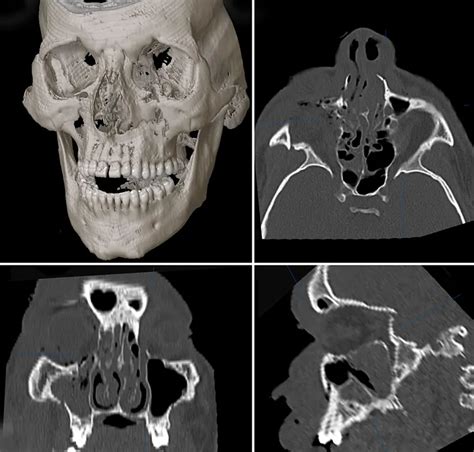

Le Fort fractures are classified into three types, based on the level of the fracture and the extent of facial involvement. Type I Le Fort fractures involve the lower part of the maxillary bone, while Type II and Type III fractures involve progressively higher levels of the face, including the nasal bones, orbits, and zygomatic arches. Accurate diagnosis is critical for determining the most effective treatment approach, and typically involves a combination of physical examination, imaging studies (such as CT scans), and clinical evaluation.

+Diagnosis of Le Fort fractures typically involves a combination of physical examination, imaging studies (such as CT scans), and clinical evaluation. Accurate diagnosis is critical for determining the most effective treatment approach.